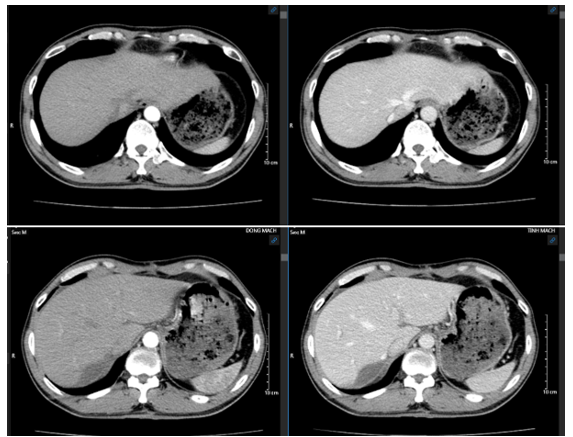

Sau điều trị 12 tháng:

Hình 5: Hình ảnh ổ tụ dịch gan phải dưới diện cắt gan/ Đã cắt phân thùy sau gan phải, không thấy khối khu trú

Như vậy: Bệnh nhân trên đây là 1 trường hợp Ung thư biểu mô tế bào gan giai đoạn BCLC C đã được điều trị bằng Lenvatinib- một thuốc điều trị đích phân tử nhỏ (TKIs), đem lại đáp ứng rất tốt thể hiện ở trên hình ảnh có thể thấy khối u giảm kích thước, không còn huyết khối tĩnh mạch cửa cũng như chỉ số AFP giảm mạnh, từ giai đoạn không thể phẫu thuật chuyển về giai đoạn có thể phẫu thuật, bệnh nhân được phẫu thuật cắt gan phân thùy sau chứa u, hiện tại bệnh ổn định, bệnh nhân được theo dõi định kì.